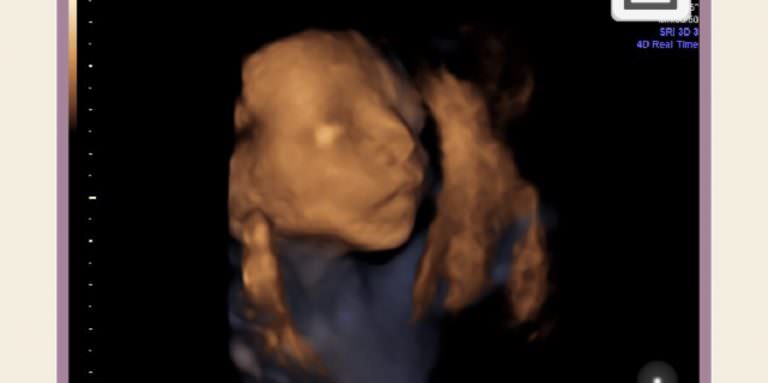

22w高層次開獎的同時,也是性別開獎的同時

是說,首圖的4D照真的超像小子的。